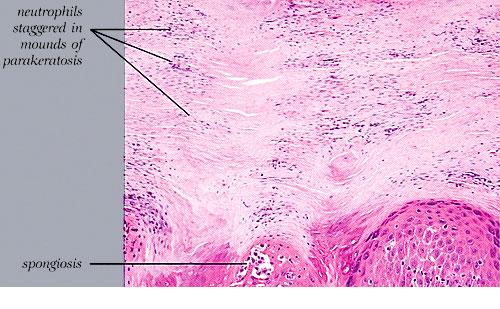

The earliest pinhead-sized macules or smooth-surfaced papules show subtle histologic changes with a preponderance of dermal changes . At first, there is capillary dilation and edema in the papillary dermis, with a lymphocytic infiltrate surrounding the capillaries. The lymphocytes extend to the lower portion of the epidermis, where slight spongiosis develops. Then focal changes occur in the upper portion of the epidermis, where granular cells become vacuolated and disappear, and mounds of parakeratosis are formed. Neutrophils are usually seen only at the summits of some of the mounds of parakeratosis and appear scattered through an otherwise orthokeratotic cornified layer . These mounds of parakeratosis with neutrophils represent the earliest manifestation of Munro microabscesses . At this stage, which is characterized clinically by an early scaling papule, a histologic diagnosis of psoriasis can often be made. In some cases, when there is marked |

exocytosis of neutrophils, they may aggregate in the uppermost portion of the spinous layer to form small spongiform pustules of Kogoj. Lymphocytes remain confined to the lower epidermis, which, as more and more mitoses occur, becomes increasingly hyperplastic. The epidermal changes are at first focal, but later become confluent, leading clinically to plaques. In the fully developed lesions of psoriasis, as best seen at the margin of enlarging plaques, the histologic picture is characterized by (a) acanthosis with regular elongation of the rete ridges with thickening in their lower portion; (b) thinning of the suprapapillary epidermis with the occasional presence of small spongiform pustules; (c) pallor of the upper layers of the epidermis; (d) diminished to absent granular layer; (e) confluent parakeratosis; (f) the presence of Munro microabscesses; (g) elongation and edema of the dermal papillae; and (h) dilated and tortuous capillaries . |

The suprapapillary epidermis appears relatively thin in comparison with the markedly elongated rete ridges, and the cells in the upper layers of the epidermis may appear enlarged and pale stained as a result of intracellular edema and hypogranulosis. Keratinocytes beneath the parakeratotic cornified layer may be intermingled with neutrophils . The histologic picture is then that of a small spongiform pustule of Kogoj . Although it is only a micropustule, it is nevertheless of the same type as the much larger macropustules seen in pustular psoriasis. Such a spongiform pustule, highly diagnostic for psoriasis and its variants, shows aggregates of neutrophils within the interstices of a spongelike network formed by degenerated and thinned epidermal cells |

Guttate or eruptive psoriasis shows the histologic features of an early or active lesion of psoriasis, where there is more pronounced inflammatory infiltrate and less acanthosis as compared with a well-developed chronic plaque of psoriasis. Because of its acute onset, one may observe the remaining normal basket-weave orthokeratotic cornified layer overlying the mounds of parakeratosis with neutrophils, which, in turn, may appear loosely arranged . |